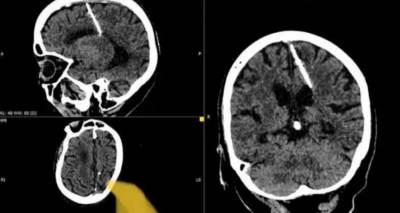

Μια βελόνα μήκους τριών εκατοστών ανακάλυψαν οι γιατροί στον εγκέφαλο μιας 80χρονης γυναίκας στη Ρωσία.